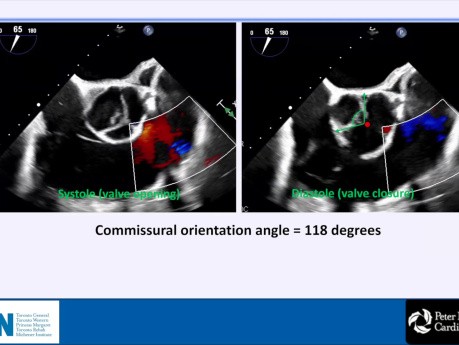

Naprawa niedomykającej się zastawki aortalnej:...

Naprawa niedomykającej się zastawki aortalnej: sztuka czy nauka? Rola przezoperacyjnej echokardiografii przezprzełykowej (TEE). Prelegent: Ahmad S. Omran MD, FACC, FESC, FASE, FEACVI. Cele: 1. Zrozumienie...